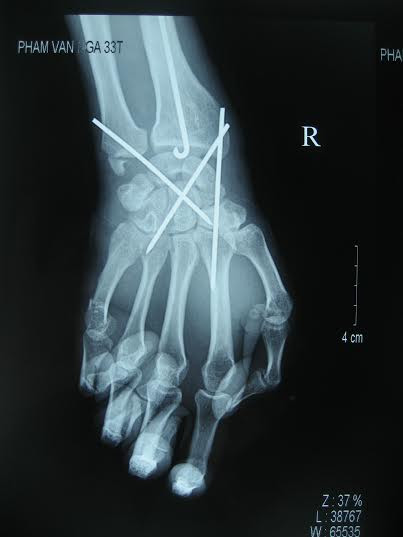

Chụp X quang trước mổ